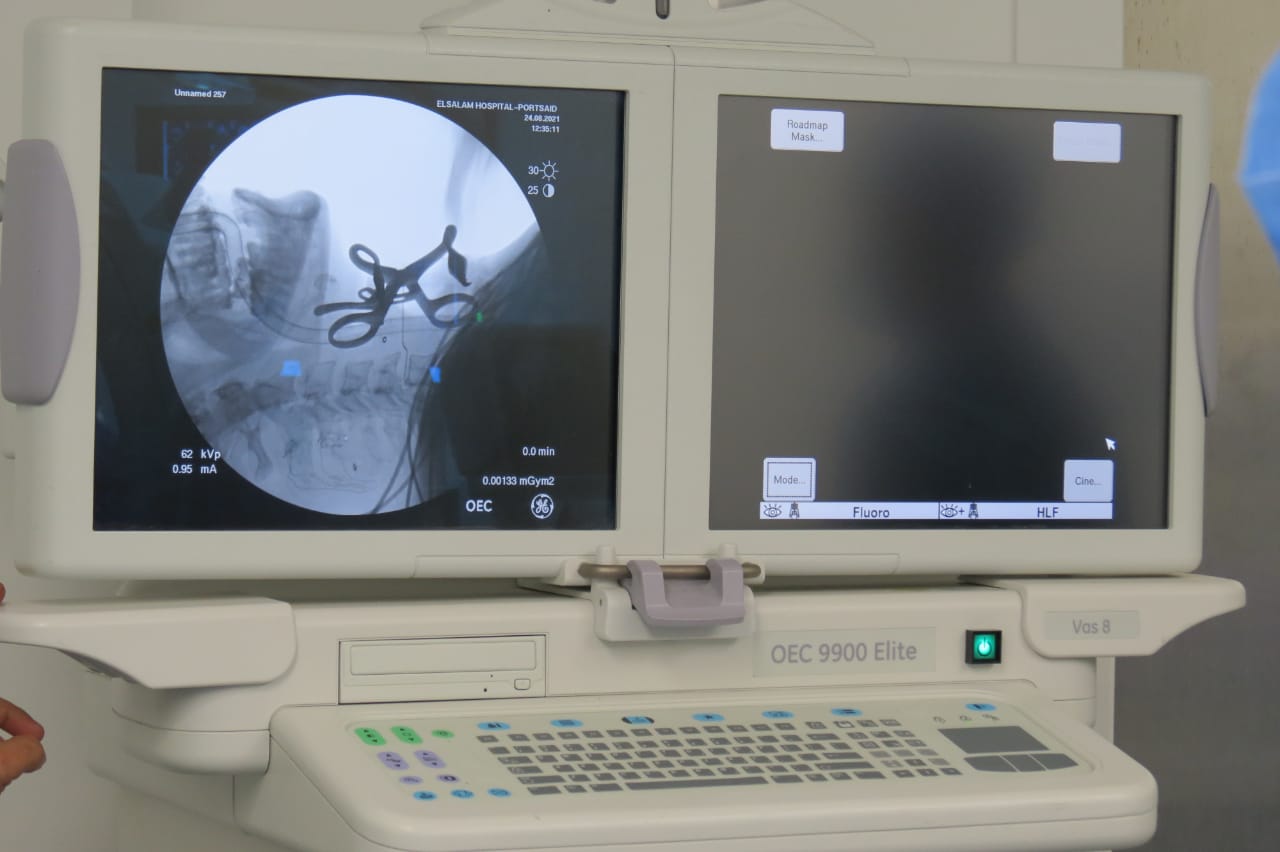

وأضافت الهيئة، أنه على الفور تم حجز المريض بالرعاية المركزة بقسم جراحة المخ والأعصاب داخل المستشفى، وتجهيزه وإدخاله غرفة العمليات وتخديره بواسطة المنظار الجراحي المتصل بالفيديو للحفاظ على ثبات الفقرات المكسورة، وإجراء التدخلات الجراحية اللازمة له حيث تمت إزالة الفقرة الخامسة العنقية المكسورة، ورفع الضغط عن الحبل الشوكي والأعصاب باستخدام الميكروسكوب الجراحي، وتركيب بديل للفقرة المكسورة من مادة التيتانيوم الطبي وتثبيتها بواسطة شريحة ومسامير، مؤكدة استقرار الحالة الصحية للمريض وتلقيه العلاج الطبيعي والدوائي الآن تحت ملاحظة ورعاية المستشفى.